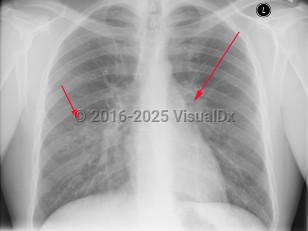

The tubercular bacilli from the infective droplet are taken up by the alveolar macrophages, particularly in the upper and mid-lung zones, which have the highest air flow rates. The breach of the bacteria into the subpleural interstitium causes a local inflammation and consolidation with an exudate and cellular infiltrate. This hallmark of primary pulmonary infection is called the Ghon focus. The bacilli are then rapidly taken up by the mediastinal lymph nodes (hilar and/or paratracheal), resulting in their enlargement and liquefaction, which liberates bacilli that can spread hematogenously throughout the body, seeding different organs. The Ghon focus and the mediastinal lymph node enlargement form the primary or Ranke complex. In most patients, the infection remains latent, being forever contained by the development of cell-mediated immunity that results within 3 weeks to 3 months in a positive skin (tuberculin) test. However, in 5%-10% of patients, mostly within 2-3 years, this initial infection evolves toward active TB. This progression is more common in immunosuppressed states such as AIDS and in children younger than 5 years. While pulmonary TB is the most common form of TB in adults and children, extrapulmonary TB can occur in any age group, although it is more common in younger age groups (eg, tuberculous lymphadenitis).

Symptoms of pulmonary TB are nonspecific and include anorexia, fatigue, anemia, weight loss, fevers, and night sweats. Cough is usually productive, and hemoptysis may occur. Pleural involvement may lead to chest pain and dyspnea. Physical examination findings include rales and signs of consolidation. Auscultation over cavities may reveal amphoric breath sounds (like the sound made by blowing across the mouth of a jar). Signs of pleural effusion may also be found. Pericarditis and pericardial effusion can occur.

The clinical manifestations of TB in HIV-infected patients correlate with the degree of immunosuppression. In general, patients with early HIV present with similar features to those without HIV. Patients with advanced HIV and TB may present with unusual manifestations such as the involvement of middle and lower lobes, negative purified protein derivative (PPD) testing, less cavitary disease, and more frequent extrapulmonary disease, especially lymphadenitis and pleurisy. In these patients, TB can also present with acute respiratory failure and acute respiratory distress syndrome. In older adults, newly acquired pulmonary TB may present with nonresolving pneumonitis of the middle and lower lobes. In countries with a high burden of HIV infection and TB, patients may present with sepsis and organ dysfunction.

Evidence of disseminated disease may be seen with a miliary pattern of lung infiltration, abnormal liver enzymes, especially alkaline phosphatase, pancytopenia, and adrenal insufficiency. Extrapulmonary sites of TB include tuberculous lymphadenitis, central nervous system involvement (eg, tuberculous meningitis [see bacterial meningitis] and/or tuberculomas [granulomatous lesions that occur by hematogenous spread of TB, often in the brain]), genitourinary TB (including the testes), and gastrointestinal TB, although almost any body location can be involved.